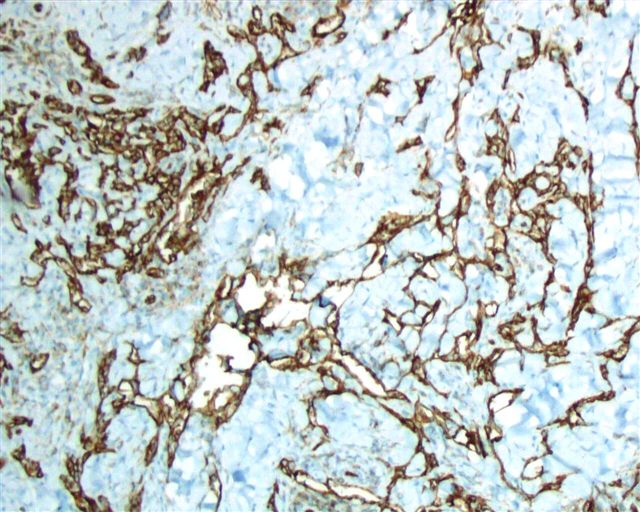

Positive stains

- CD31: membranous staining

- CD34: membranous staining

- Claudin5: cytoplasmic staining (Am J Surg Pathol 2011;35:1848)

- VEGFR2: membranous staining (Am J Surg Pathol 2012;36:629)